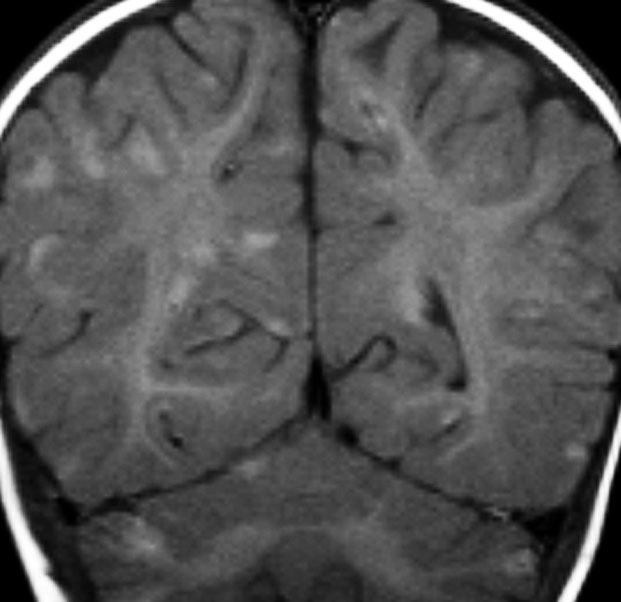

水頭症とけいれん発作で発症した例

年長児例でけいれん発作と水頭症で発症した子どもです。中央の画像に見えるように,脳幹部の周囲が線状に白く増強されています。頭頂部にはゴロンとした腫瘤形成があり,これは悪性黒色腫 メラノーマだと考えられます。